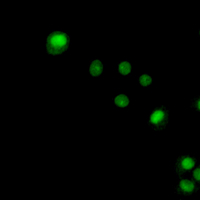

Immunofluorescent analysis of NKX2-1 staining in Hela cells. Formalin-fixed cells were permeabilized with 0.1% Triton X-100 in TBS for 5-10 minutes and blocked with 3% BSA-PBS for 30 minutes at room temperature. Cells were probed with the primary antibody in 3% BSA-PBS and incubated overnight at 4 °C in a hidified chamber. Cells were washed with PBST and incubated with a AF488-conjugated secondary antibody (green) in PBS at room temperature in the dark.